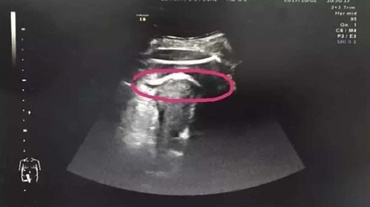

Manushi este unul dintre cei mai mici nou-născuţi din lume care a supravieţuit. Micuţa indiancă s-a născut prematur, cu 12 săptămâni înainte de termen, având o...